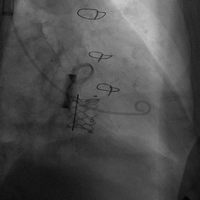

病例一(经右心房三尖瓣瓣中瓣)

患者女性,68岁,既往行三尖瓣生物瓣置换术,二尖瓣机械瓣置换术,三尖瓣位置入佰仁思29#瓣膜一枚。STS评分9.69%,属于外科换瓣手术高风险患者。术前心脏超声示原三尖瓣生物瓣中量反流。术前详尽评估,经股静脉路入同轴性不理想,且右颈静脉既往手术存在瘢痕狭窄,故术中选择腋下小切口途径,通过右心房穿刺植入27# Renato球扩式瓣中瓣,释放成功后瓣膜功能良好,无明显瓣中及瓣周反流,平均跨瓣压差0.5mmHg。

瓣膜释放